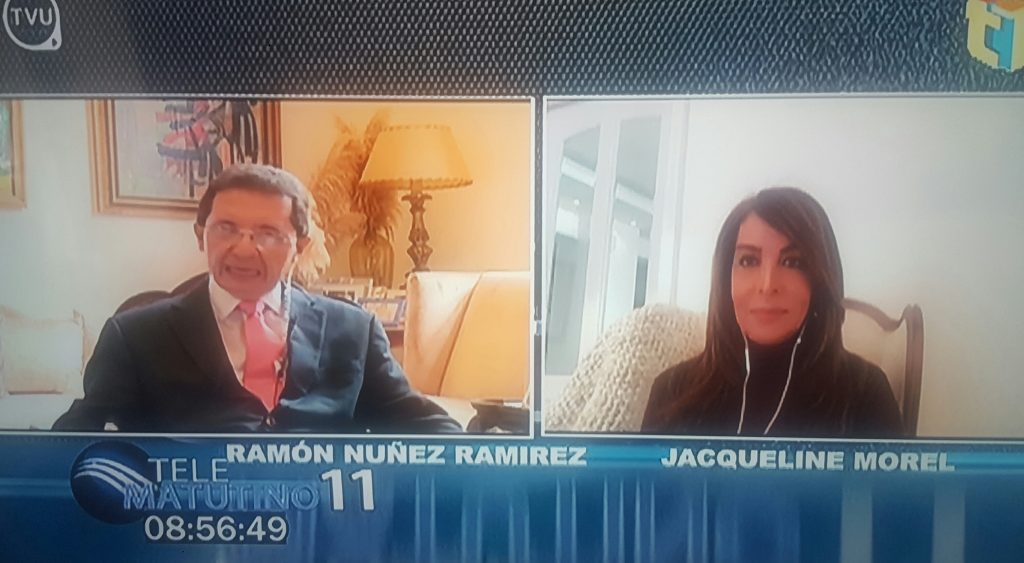

Jorge Marte Báez, quien además es asesor del Poder Ejecutivo en materia de salud, durante una entrevista telefónica para el programa Telematutino 11, que conducen los periodistas Ramón Núñez Ramirez y Jacqueline Morel.

El programa de televisión se transmite de lunes a viernes de 8:00 a 9:00 de la mañana, por Telesistema, canal 11.